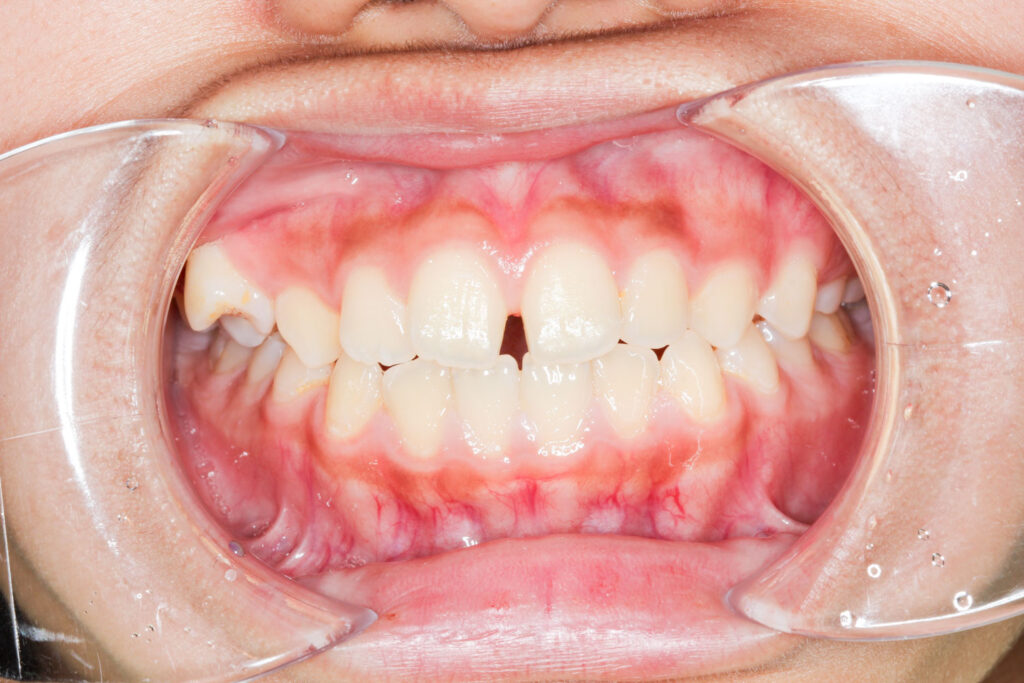

Before

After

年齢 10代

治療装置 上は裏側の矯正装置(フルリンガル)

治療内容 非抜歯

治療期間 2年8か月

リスク 歯の移動に伴う痛み、歯肉退縮、歯根吸収、歯肉炎、虫歯

主訴 ガタガタと隙間が気になる

症状 叢生と正中離開

治療回数 36回程度

総額費用 140万円程度